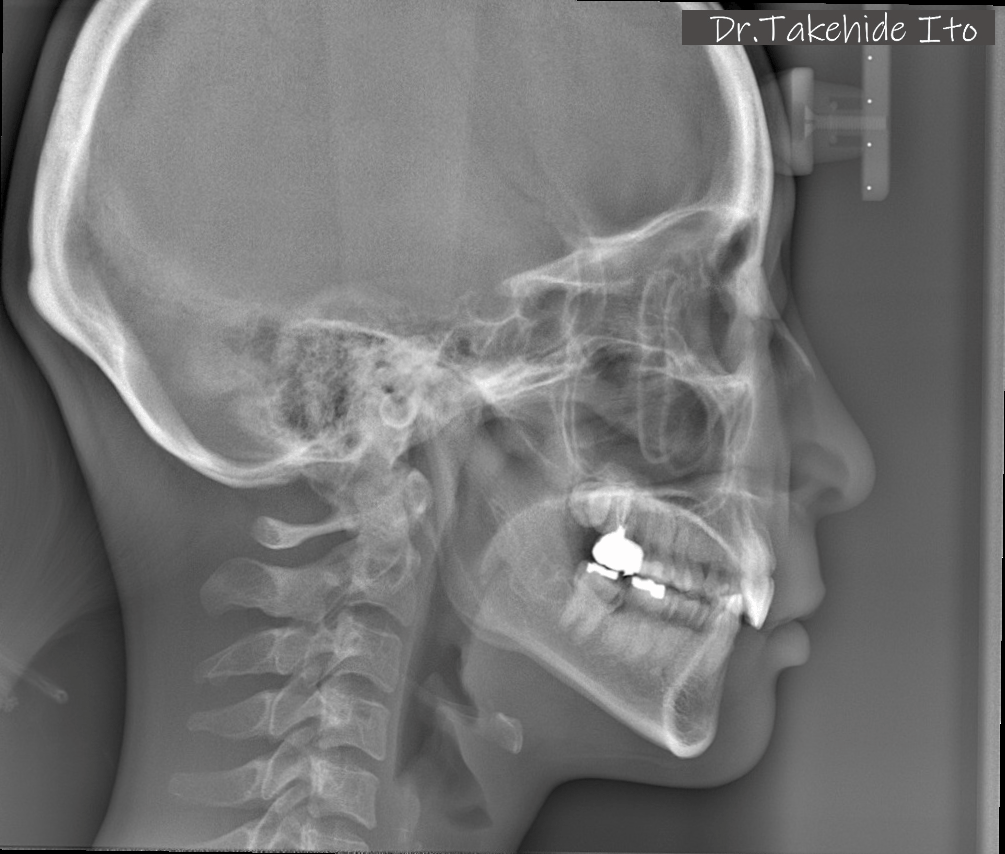

当院では、体の歪みを調べ、その方にとって無理のない安定した顎位を見つけ出し、その位置で噛み合わせを構築することを重要視した矯正治療を行っています。

また、歯列矯正だけではなく、全顎的に歯の治療(補綴治療)を必要とする方も体の歪みをみる上で治療をすることがとても重要です。